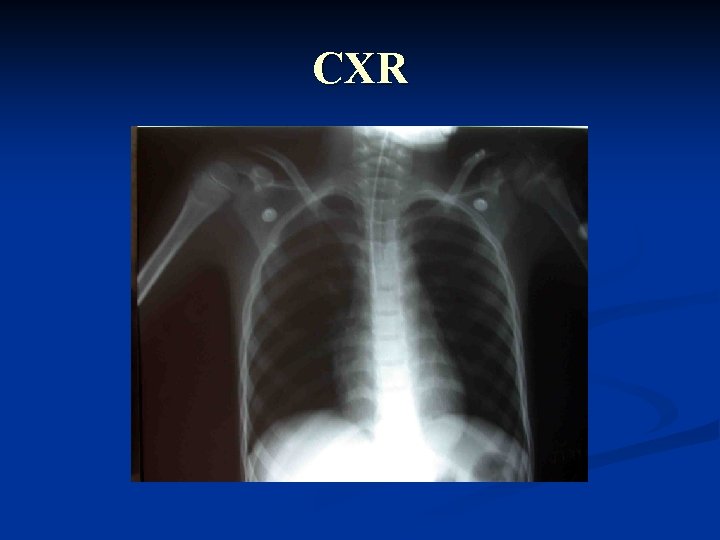

CXR